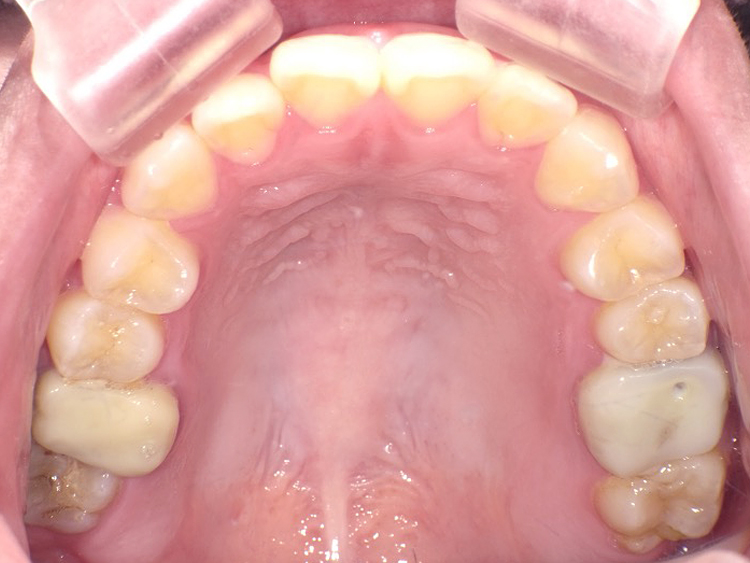

症例3

Before

After

| 主訴 | 上下の歯のガタガタを治したい |

|---|---|

| 年齢 | --- |

| 治療期間 | 約10ヶ月 |

| 治療内容 | インビザラインiGoで上下顎の治療。 狭まっていた歯並びを広げることで、 ガタガタに並んでいた歯を綺麗に並べた。 |

| 治療費 | ¥517,000(税込)+月額調整料 |

| 治療のリスク | 歯と歯の間を削ることでスペースを確保するので、 場合によっては歯が染みる症状が出ることがある。 |